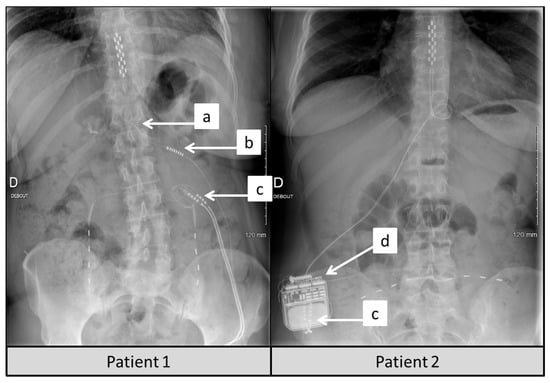

2.3. Procedures and Additional PNfS Implantation

4.4. Technical Considerations to Take into Account, When Converting a Patient Already Implanted with SCS to SCS + PNfS